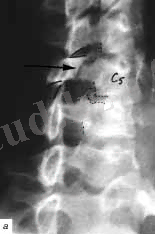

Рис. 2. Омыртқаның мойын бөлімінің Рентгеногграммасы

а- схема, б - хэнгман сынығы ( «асылған »), в - С2 омыртқа тісінің сынығы

Радиологиялық зерттеулер. Тексеруді көрсеткіш екі проекциялы ретгенннен бастайды, алдыңғы артқы және бүйір, рентгенограмманың ортасында клинасмен анықталған зақымданған ошақ орналасады. Алдынғы артқы проекцияда көлденең өсінділер зақымдануы, омыртқалардың бүйірлык шығулары, ал қалған сынықтар бүйір проекцияда жақсы көрінеді. Әдеттегі сынықтардардың орнын білу кезінде рентгенологиялық тексеру барысында барлық кеуде бел ауысуын (бел омыртқаларының сынығына күдіктенгенде ) және мойын- кеуде ауысуында төменгі мойын омыртқаларының сынығын анықтағанда, науқас қолы төменге қарай, иық және иықүсті буының төмен түсіру арқылы рентген суретін жасаймыз. Рентгенограмманы бағалаған соң, керек жағдайда томограммыа, қиғаш проекциялы рентгенограмма, жасауға болады, Омыртқаның шығуы болатын болса, жоғары орналасқан омыртқа шыққан деп есептеледі. (рис. 5 а, б)

Омыртқа денесінің сынығының рентгендік көрінісі ретінде бүйір проекциядағы сына тәрізді деформация болып табылады. (рис. 5, в) .

Рис. 5. омыртқа зақымлдануы кезінде рентегн зерттеуі.

а -С3 омыртқасының алдыға қарай шығуы, б - С5омыртқасының малдыға шығуы, в - компрессионный перелом II L2 омыртқа денесінің II дәрежелі компрессиялы сынығы